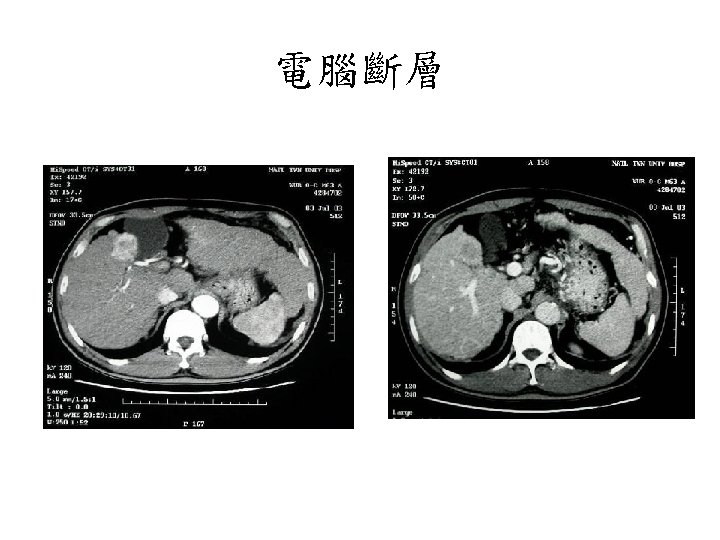

電腦斷層 • 篩檢為陽性的病人,作為第一線診斷 具 • 建議使用動態影像 (Triphasic image) – Arterial phase: enhanced – Portal-venous

電腦斷層 • 篩檢為陽性的病人,作為第一線診斷 具 • 建議使用動態影像 (Triphasic image) – Arterial phase: enhanced – Portal-venous and/or delayed phases: washout